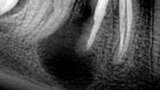

Figura 2. Lesión periapical en el diente 46 (primer molar inferior derecho) de gran tamaño. Iniciando una reabsorción radicular externa en la raíz distal.